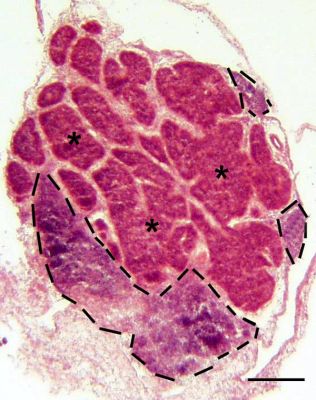

Histology of the pineal gland. Frozen section of the pineal gland stained with H&E. The pineal follicles (*) comprise pinealocytes and supportive cells arranged as epithelium. Prominent interstitial septa separate individual follicles. Several large accumulations of mononuclear (MN) cells, forming the PALT (bordered by the dashed black lines) are seen. Bar indicates 200 μm.